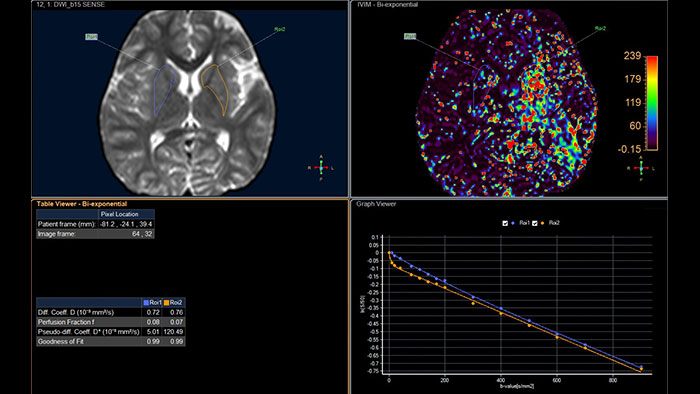

Enhance your workflow by generating additional cDWI (calculated) images with b-values that were not acquired

MR Advanced Diffusion Analysis (ADA) is a post processing software application used to view, process and analyze MRI Diffusion Weighted Images. The application calculates and displays cDWI at a b-value of choice and provides advanced supportive analysis and visualization tools of diffusion MRI images and parametric maps.